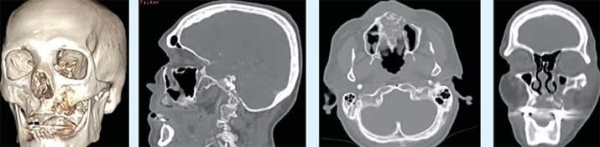

Для лучевой диагностики необходимо проведение КЛКТ и МСКТ челюстно-лицевой области, дополненные внутривенным болюсным контрастным усилением для детальной оценки кровотока в пораженной зоне. Дополнительно проводится КТ органов грудной полости, живота и малого таза при выявлении распространения. Следует отметить, что конусно-лучевая компьютерная томография (КЛКТ) зубочелюстной системы значительно более информативна при диагностике этих поражений, нежели мультиспиральная компьютерная томография (МСКТ).

В лучевой диагностике мы увидим на фоне заболевания остеонекроз в бассейне верхнечелюстной артерии (см. фото 2–3). Это ранние признаки проявления некроза, которые четко указывают на то, что ждать больше нельзя — требуется хирургическое устранение очага. В ином случае омертвление тканей будет распространяться дальше.

Фото 2. МСКТ костей лицевого отдела черепа и сагиттальная проекция. Остеонекроз в бассейне левой верхнечелюстной артерии.

Фото 3. КЛКТ в просмотровом режиме MPR. Остеонекроз альвеолярного отростка справа, стенок правой верхнечелюстной пазухи, решетчатой кости справа, нижней и медиальной стенок правой орбиты.